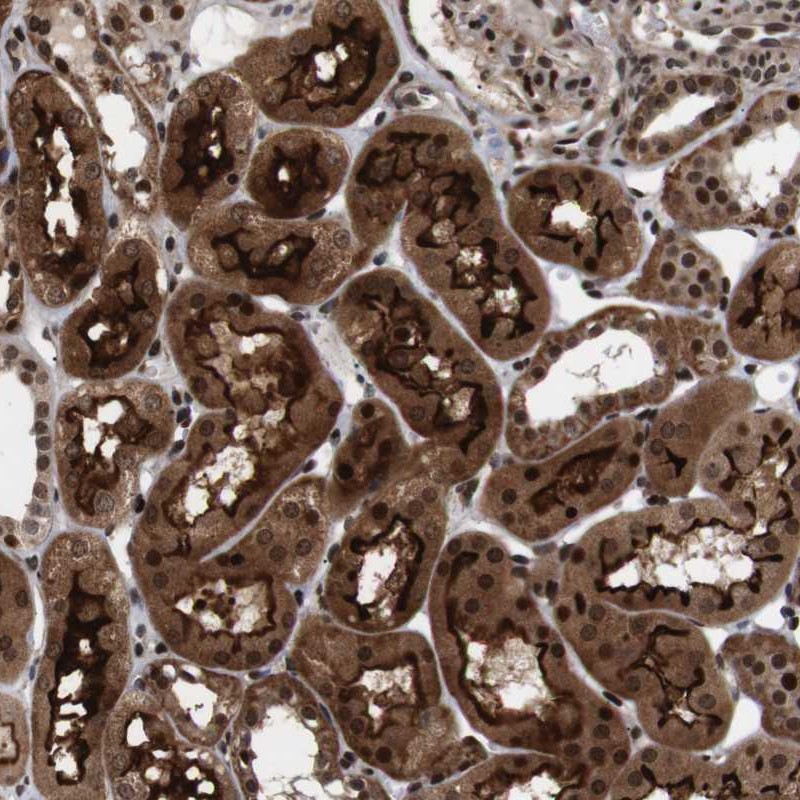

- Immunohistochemical staining of human kidney shows strong cytoplasmic, membranous and nuclear positivity in cells of tubules.

- Staining pattern partly consistent with experimental and/or bioinformatic data.